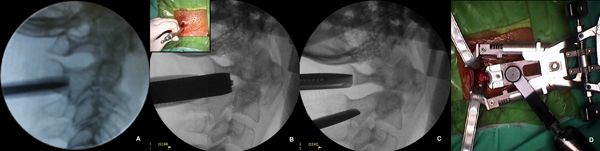

Una semana antes de la cirugía, se les colocó a ambos pacientes, con guía radioscópica, un halo-chaleco cervical para lograr la reducción de la fractura (Figura 2) y evitar un mayor desplazamiento del fragmento durante el posicionamiento quirúrgico y en consecuencia, evitar un potencial daño neurológico.

Figura 2. Reducción y estabilización de la fractura.

A. y B. Halo-chaleco colocado. C. Se observa el desplazamiento posterior del fragmento odontoideo previo a la inmovilización. D. Alineación de la fractura luego de la colocación del halo-chaleco

El paciente es posicionado, con el halo- chaleco colocado, en decúbito dorsal (Figura 3A).

Incisión

Se marcan dos incisiones paramedianas a 2 cm de línea media (lo cual se corresponde con la proyección axial de las facetas) de 2,5 - 3 cm de longitud, centradas en el interespacio C1-C2 (Figura 3B y 3C).

Colocación del retractor tubular

Luego de la disección del tejido celular subcutáneo (TCS) y la apertura de la fascia de la musculatura paravertebral, se coloca el dilatador más pequeño, direccionándolo al borde superior de la faceta de C2 (Figura 4A). Se debe tener cuidado en no profundizar este dilatador en el espacio comprendido entre el arco de C1 y la lámina de C2.

Se continúa con los dilatadores secuenciales hasta colocar el retractor tubular expansible de 12mm (Maxcess IV) sobre la masa lateral de C2 (Figura 4B). A continuación, el retractor es dirigido hacia cefálico y se lo expande hasta visualizar el área entre el arco posterior de C1 y la masa lateral de C2 (Figura 4C). Una tercera rama del distractor se utiliza para separar lateralmente la musculatura (Figura 4D).

Figura 3. Posicionamiento y marcación de la incisión.

A. Paciente posicionado en decúbito ventral, con los hombros a ambos lados del cuerpo y realce en tórax y ambas crestas ilíacas. B. Incisiones paramedianas de 3 cm de longitud. La línea punteada negra indica la línea media. C. Radioscopía, plano coronal. La línea punteada marca la posición de las masas laterales, y se corresponde con la incisión en piel.

Figura 4. Colocación del retractor tubular.

A. - C. Imagenes de radioscopía intraoperatoria, donde se observa: el dilatador inicial sobre la faceta de C2 (A.). Luego de la dilatación secuencial (B.), y la apertura de las 3 ramas del retractor expansible, hasta exponer el área deseada (C.). El recuadro interior de B. muestra una imagen intraoperatoria de los dilatadores secuenciales. D. Vista panorámica superior del retractor Maxcess IV colocado en el campo quirúrgico.